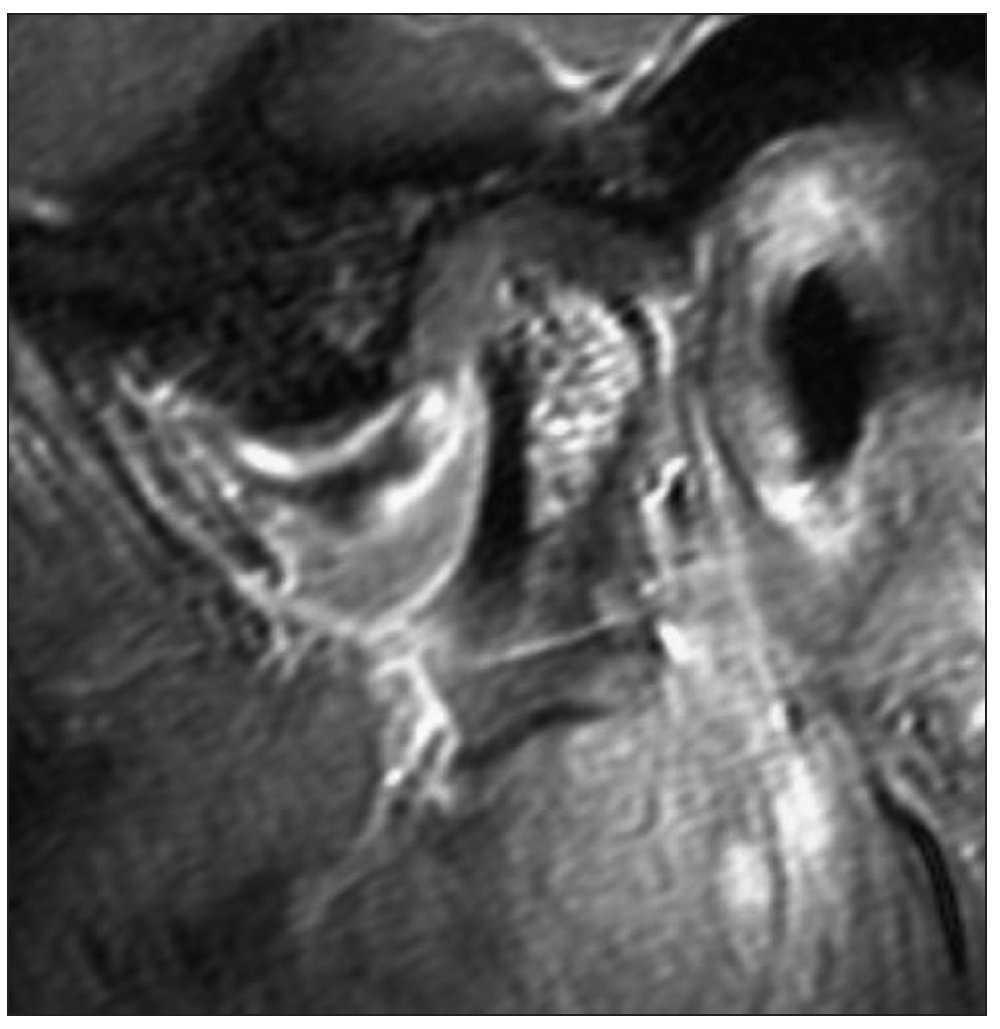

Se obtuvo una resonancia magnética de las articulaciones temporomandibulares debido a los signos de erosión existentes en el cóndilo derecho. Con la boca cerrada, se observa un desplazamiento discal anterior en el lado derecho y también la erosión anteriormente descrita de la sustancia compacta ventral del cóndilo (fig. 3). Al alcanzar la máxima apertura bucal, el disco es desplazado más hacia ventral (fig. 4). Este hallazgo es un signo patognomónico de un desplazamiento discal anterior sin reducción.

Figura 3. Resonancia magnética-plano oblicuo sagital con boca cerrada.